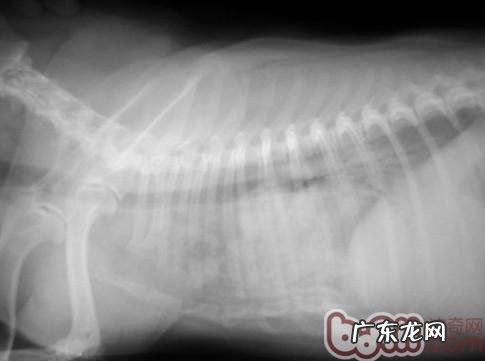

它是一只10岁的雌虫巴哥犬 。因喘气比较严重就医 。下面的图是该心脏疾病患犬的胸骨右边位X线片 。

肺野相对密度明显上升

它是一张规范的病重等级X线片,肺野相对密度高,心血管呈云絮状物黑影,轮廊早已没法识别,由此可见气体支气管炎征 。而心源性急性肺水肿在X线片一般先主要表现在肺部地区,这张X线片早已表明这只犬的病情恶化水平早已做到随时随地很有可能身亡的水平 。但是主人家并沒有放弃医治 。在历经三天的医治后,患犬临床医学情况明显改善,喘气缓解,复诊其胸骨侧方X线片以下: